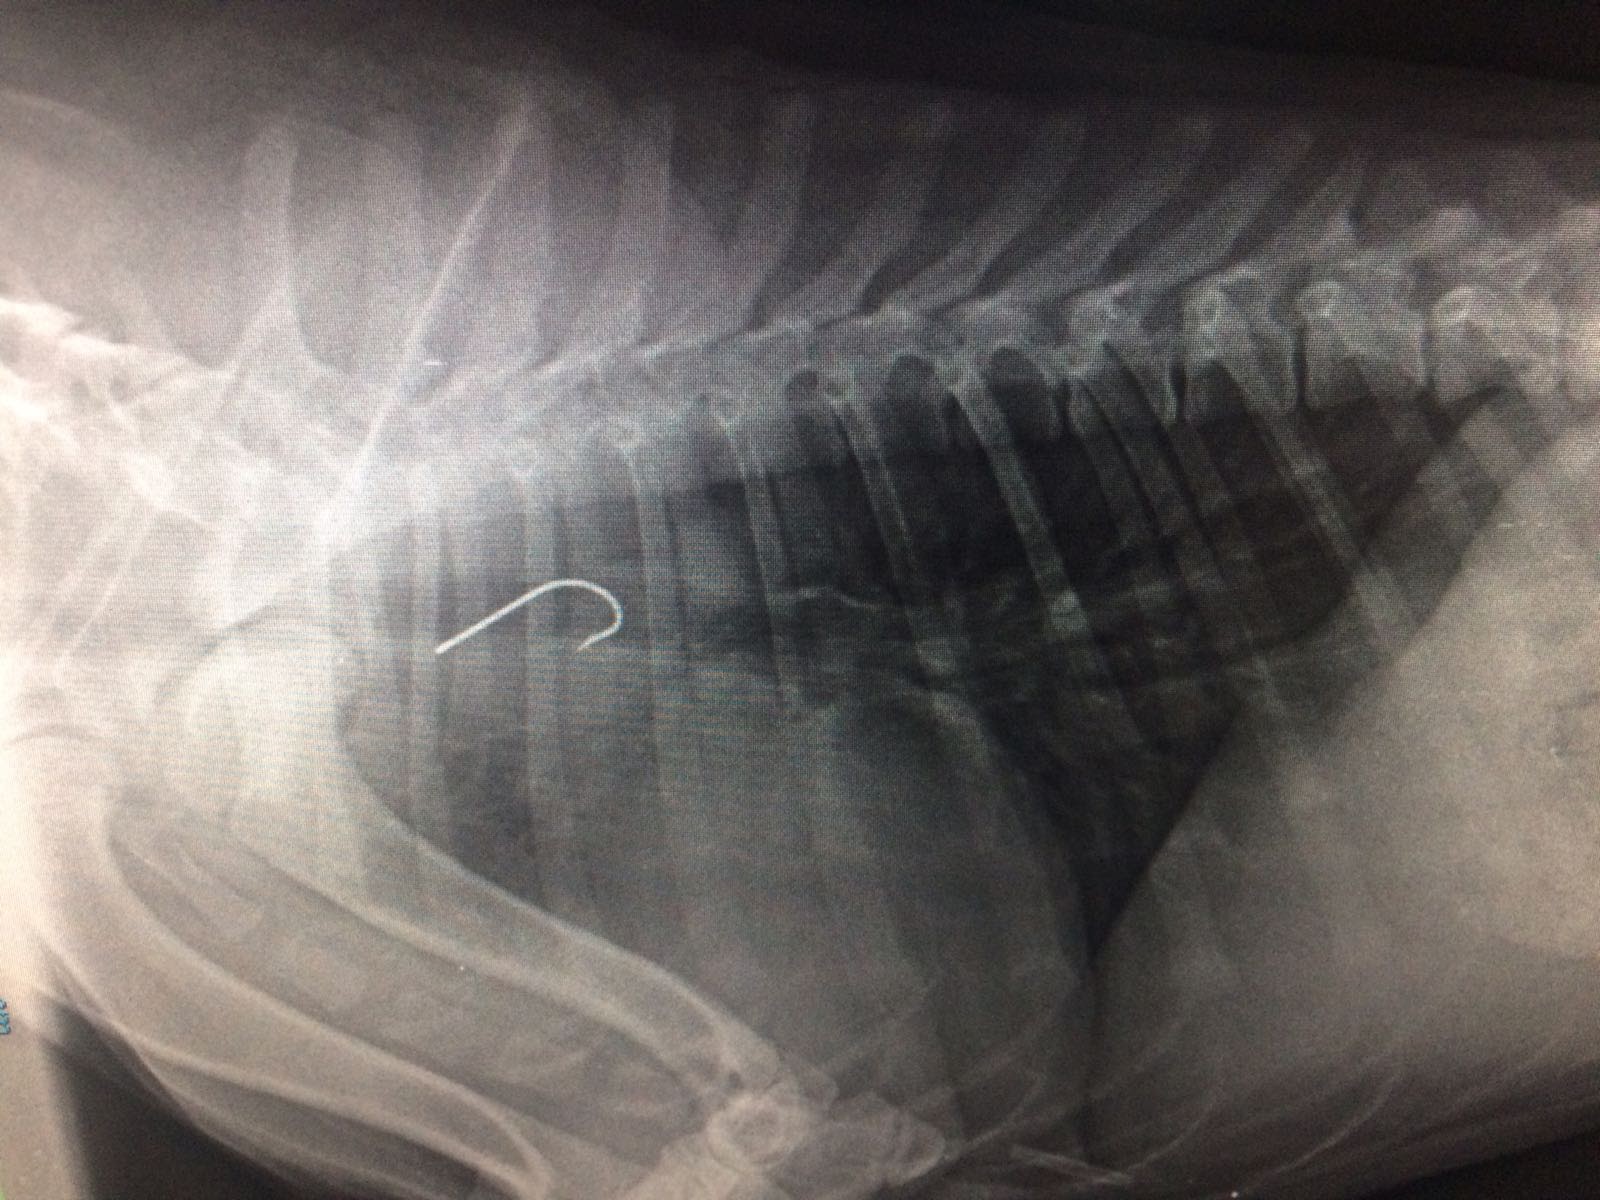

Anzuelo en esófago torácico: esofagotomía de urgencia

RADIO POST QUIRURGICA